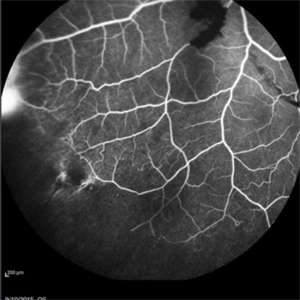

Angiography showed normal vessels posteriorly but severe capillary drop out throughout the periphery OU with scattered severe neovascularization at the edge of the capillary drop out peripherally.

Sickle Cell Retinopathy Sickle Cell RetinopathySep 13 2015 by Thomas A. Ciulla, MD, MBA, FASRS Angiography showed normal vessels posteriorly but severe capillary drop out throughout the periphery OU with scattered severe neovascularization at the edge of the capillary drop out peripherally. Photographer: Thomas Steele Condition/keywords: peripheral retinal neovascularization, sea fan, sickle cell retinopathy